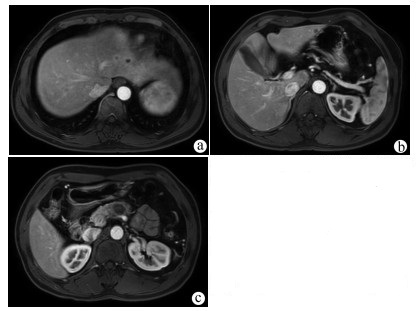

Solitary fibrous tumor of the liver: A case report

Xuecheng LI, Ying FAN, Shuodong WU

2022, 38(3): 632-633. DOI: 10.3969/j.issn.1001-5256.2022.03.026

Abstract(803) HTML (221) PDF (2657KB)(58)

Abstract: